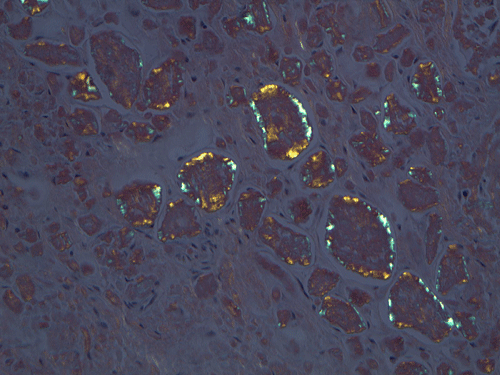

On low magnification, the mucosa appear intact and unremarkable. However, the submosa and muscular layer is replaced by a pale eosinophilic, hypocellular, amorphous material (Panel A). These material separate the smooth muscle bundles (Panel B and C). On Masson's trichrome, these material appears blue (Panel D). They are negative for elastic stain (Panel E). These material are stained orange by Congo Red stain (Panel F and G) which gives an apple green birefrigence on polarized light (Panel H). Electron microscopy was performed and revealed non-branhing straight fibrils ranging from 6.6 to 8.3 nm in diameter consistent with amyloid.

Immunohistochemistry was performed and showed strong reactivity for lambda light chain. Numerous plasma cells within the mucosa overlying the amyloid deposition are also postive for lambda light chains. The results suggest a monoclonal lambda light chain plasma cell dyscrasia but it could not be further classified in the excised specimen.